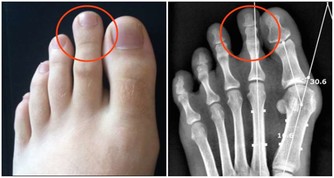

狐臭如何產生人體的汗腺有兩種,一種是小汗腺(外分泌腺),分布全身,功能是分泌汗水排除體熱,調節體溫。

一種是大汗腺(頂漿腺),主要分布在腋下、陰部、肛門、乳頭和肚臍等周圍,

會分泌黏稠乳黃色的液體,與體溫調節無關,但與個人體味有關。

當頂漿腺的分泌液被腋窩皮膚表面的細菌分解後,會產生一股惡臭的味道,即所謂的狐臭。